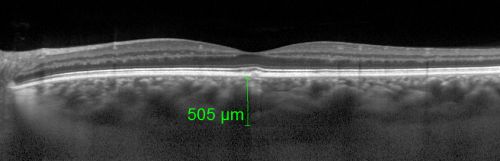

Central Serous Retinopathy Acute - Enhanced Depth Imaging OCT - Thickened Choriod

42-year-old man was seen in the office on October 5, 2011.  He had noticed starting in August after a course of antibiotic and steroids, that he developed new spots in his vision in the right eye.  He may have had an episode like this sometime in the past.  He did take steroids a few years ago and his vision did change at that time, but then returned.

VISUAL ACUITY:  OD 20/32,  OS 20/32